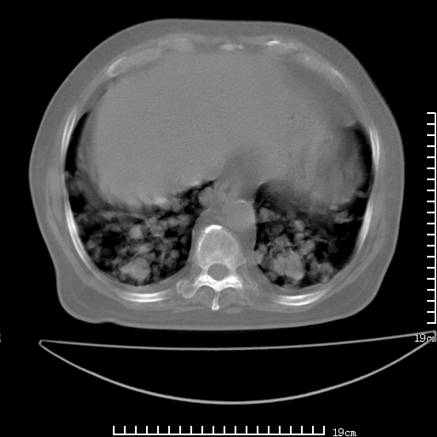

张男,75岁,干咳半年余,小便不利二年,b超检查前列腺增大,未见明显肿块;前列腺癌血生化检查多项指标明显增高。

双肺内多发转移瘤,纵膈淋巴结转移。来源前列腺?建议盆腔mri进一步检查。

双肺转移满了。

两肺广泛转移瘤。